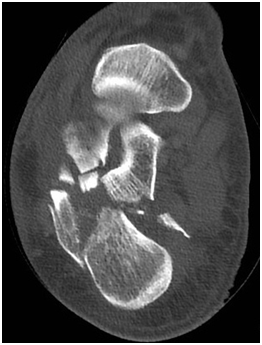

Radiological assessment shows

L3 unstable spine fracture, Right intara-articular calcaneal fracture of joint depression type, Saunder’s III AC3,4(Figure 1 & 2).

Figure 1 CT Calcaneus showing multi fragmentery intra articular fracture.

Figure 2 CT Calcaneus showing joint depression and intra articular extension.